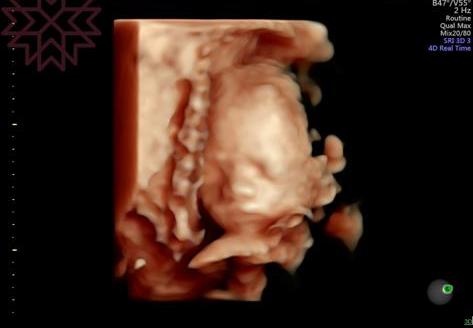

今天進行了第三次的產檢,雖然已經看了很多次螢幕上『外星人』樣的寶寶,但每次照超音波時都還是無比的期待。今天的寶寶依舊活潑,難怪我常常可以感覺到他動來動去,很像不用睡覺ㄧ樣;寶寶有乖乖的長大,但體重好像比平均值來的低,頭圍也比平均值小了些,但都在正常的範圍,照3D圖時也可以清楚的看見五官囉,好像有點像我。至於上次產檢發現的前置胎盤還是沒有移動位置,而且好像是所謂的完全性前置胎盤,目前能做的就是每次產檢的追蹤,若有任何出血的症狀,要馬上就醫;我有在網路上看到一些注意事項,然後就是希望30週後胎盤能夠慢慢的回到正常的位置。

附上我們家的小帥哥特寫